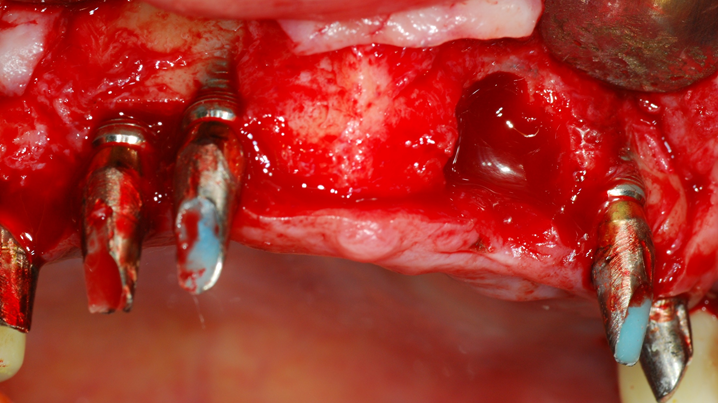

“Achieving a clean surface is the key to treating peri-implantitis!Using a titanium or NiTi brush for the decontamination process along with proper GBR can successfully restore the peri-implant environment. ”

Clinical case: Peri-implantitis treatment case using titanium or NiTi brush

- Courtesy of Dr. Dae-Hee Lee, South Korea -

Dr. Dae-Hee Lee,Maxillary Anterior,Peri-implantitis,Bone regeneration,Aesthetic zone,#21,#22,GBR,Titanium Brush Set